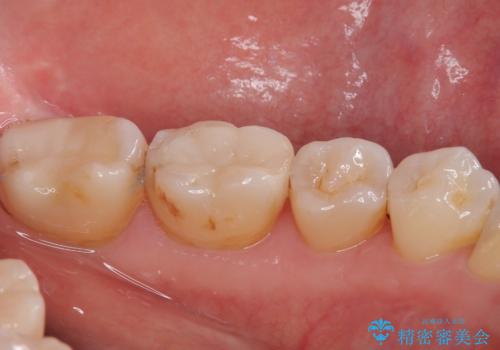

歯と歯茎の間に圧排糸と言われる糸を入れてシリコーン印象材にて精密な型どりをしました。

セラミックインレーの装着時には、唾液の侵入を防ぐために、ラバーダム防湿を行いました。

特に異常もなく見た目、噛み合わせともに満足していただけました。

ラバーダム防湿を行い、セラミックの接着をすることで、唾液や血液などの接着阻害因子を排除することができます。